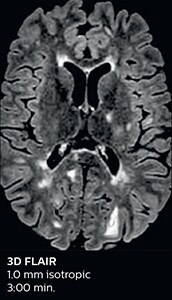

Ultimate precision at maximum speed with Dual AI

Take the leap forward with SmartSpeed Precise, the next generation acceleration technique that expands the proven Compressed SENSE and SmartSpeed technologies with a unique integrated Dual AI innovation, providing ultimate precision at maxiumum speed.

Read more

SmartSpeed Precise